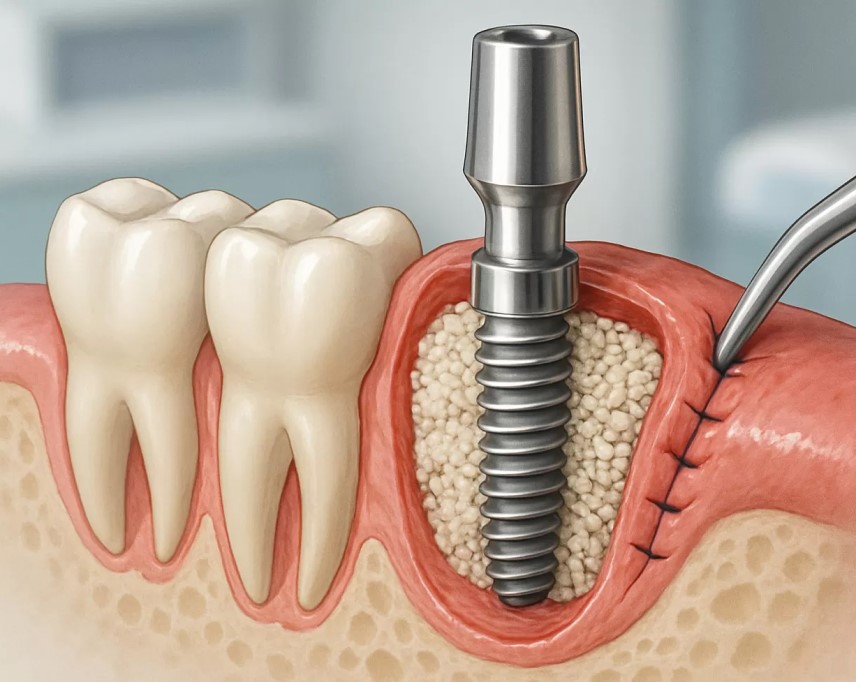

مراحل کاشت ایمپلنت دندان در ونک، ایمپلنت دندان یکی از پیشرفتهترین روشهای جایگزینی دندانهای از دست...

عوارض احتمالی و ریسکهای مرتبط با پیوند استخوان در جراحی ایمپلنت در ونک. امروزه کاشت ایمپلنت دندان به...

انواع روش های پیوند استخوان و مزایا و معایب هر کدام در کاشت ایمپلنت دندان در ونک. بازسازی استخوان یکی...